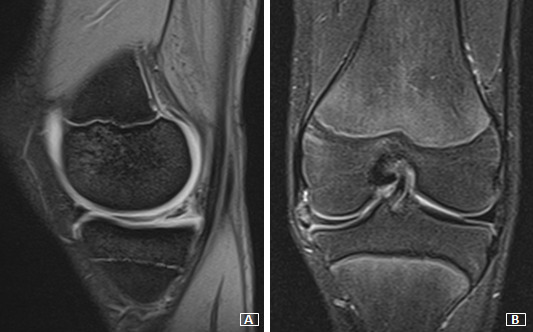

MRI of both knees showed an enlarged saucer-like appearance of the medial meniscus in the coronal plane, extending into the intercondylar notch. In addition, a sizeable horizontal tear involved the posterior horn of the left knee’s medial meniscus, and intrasubstance degeneration signals were found in the right knee medial meniscus. MRI of the left knee also demonstrated the appearance of meniscal subluxation in the coronal plane (Figures 1 and 2).

_and_coronal_(b)_t2-weighted_mri_sections_of_the_right_knee__showing_incomplet.png)

_and_coronal_(b)_t2-weighted_mri_sections_of_the_left_knee__showing_incomplete.png)